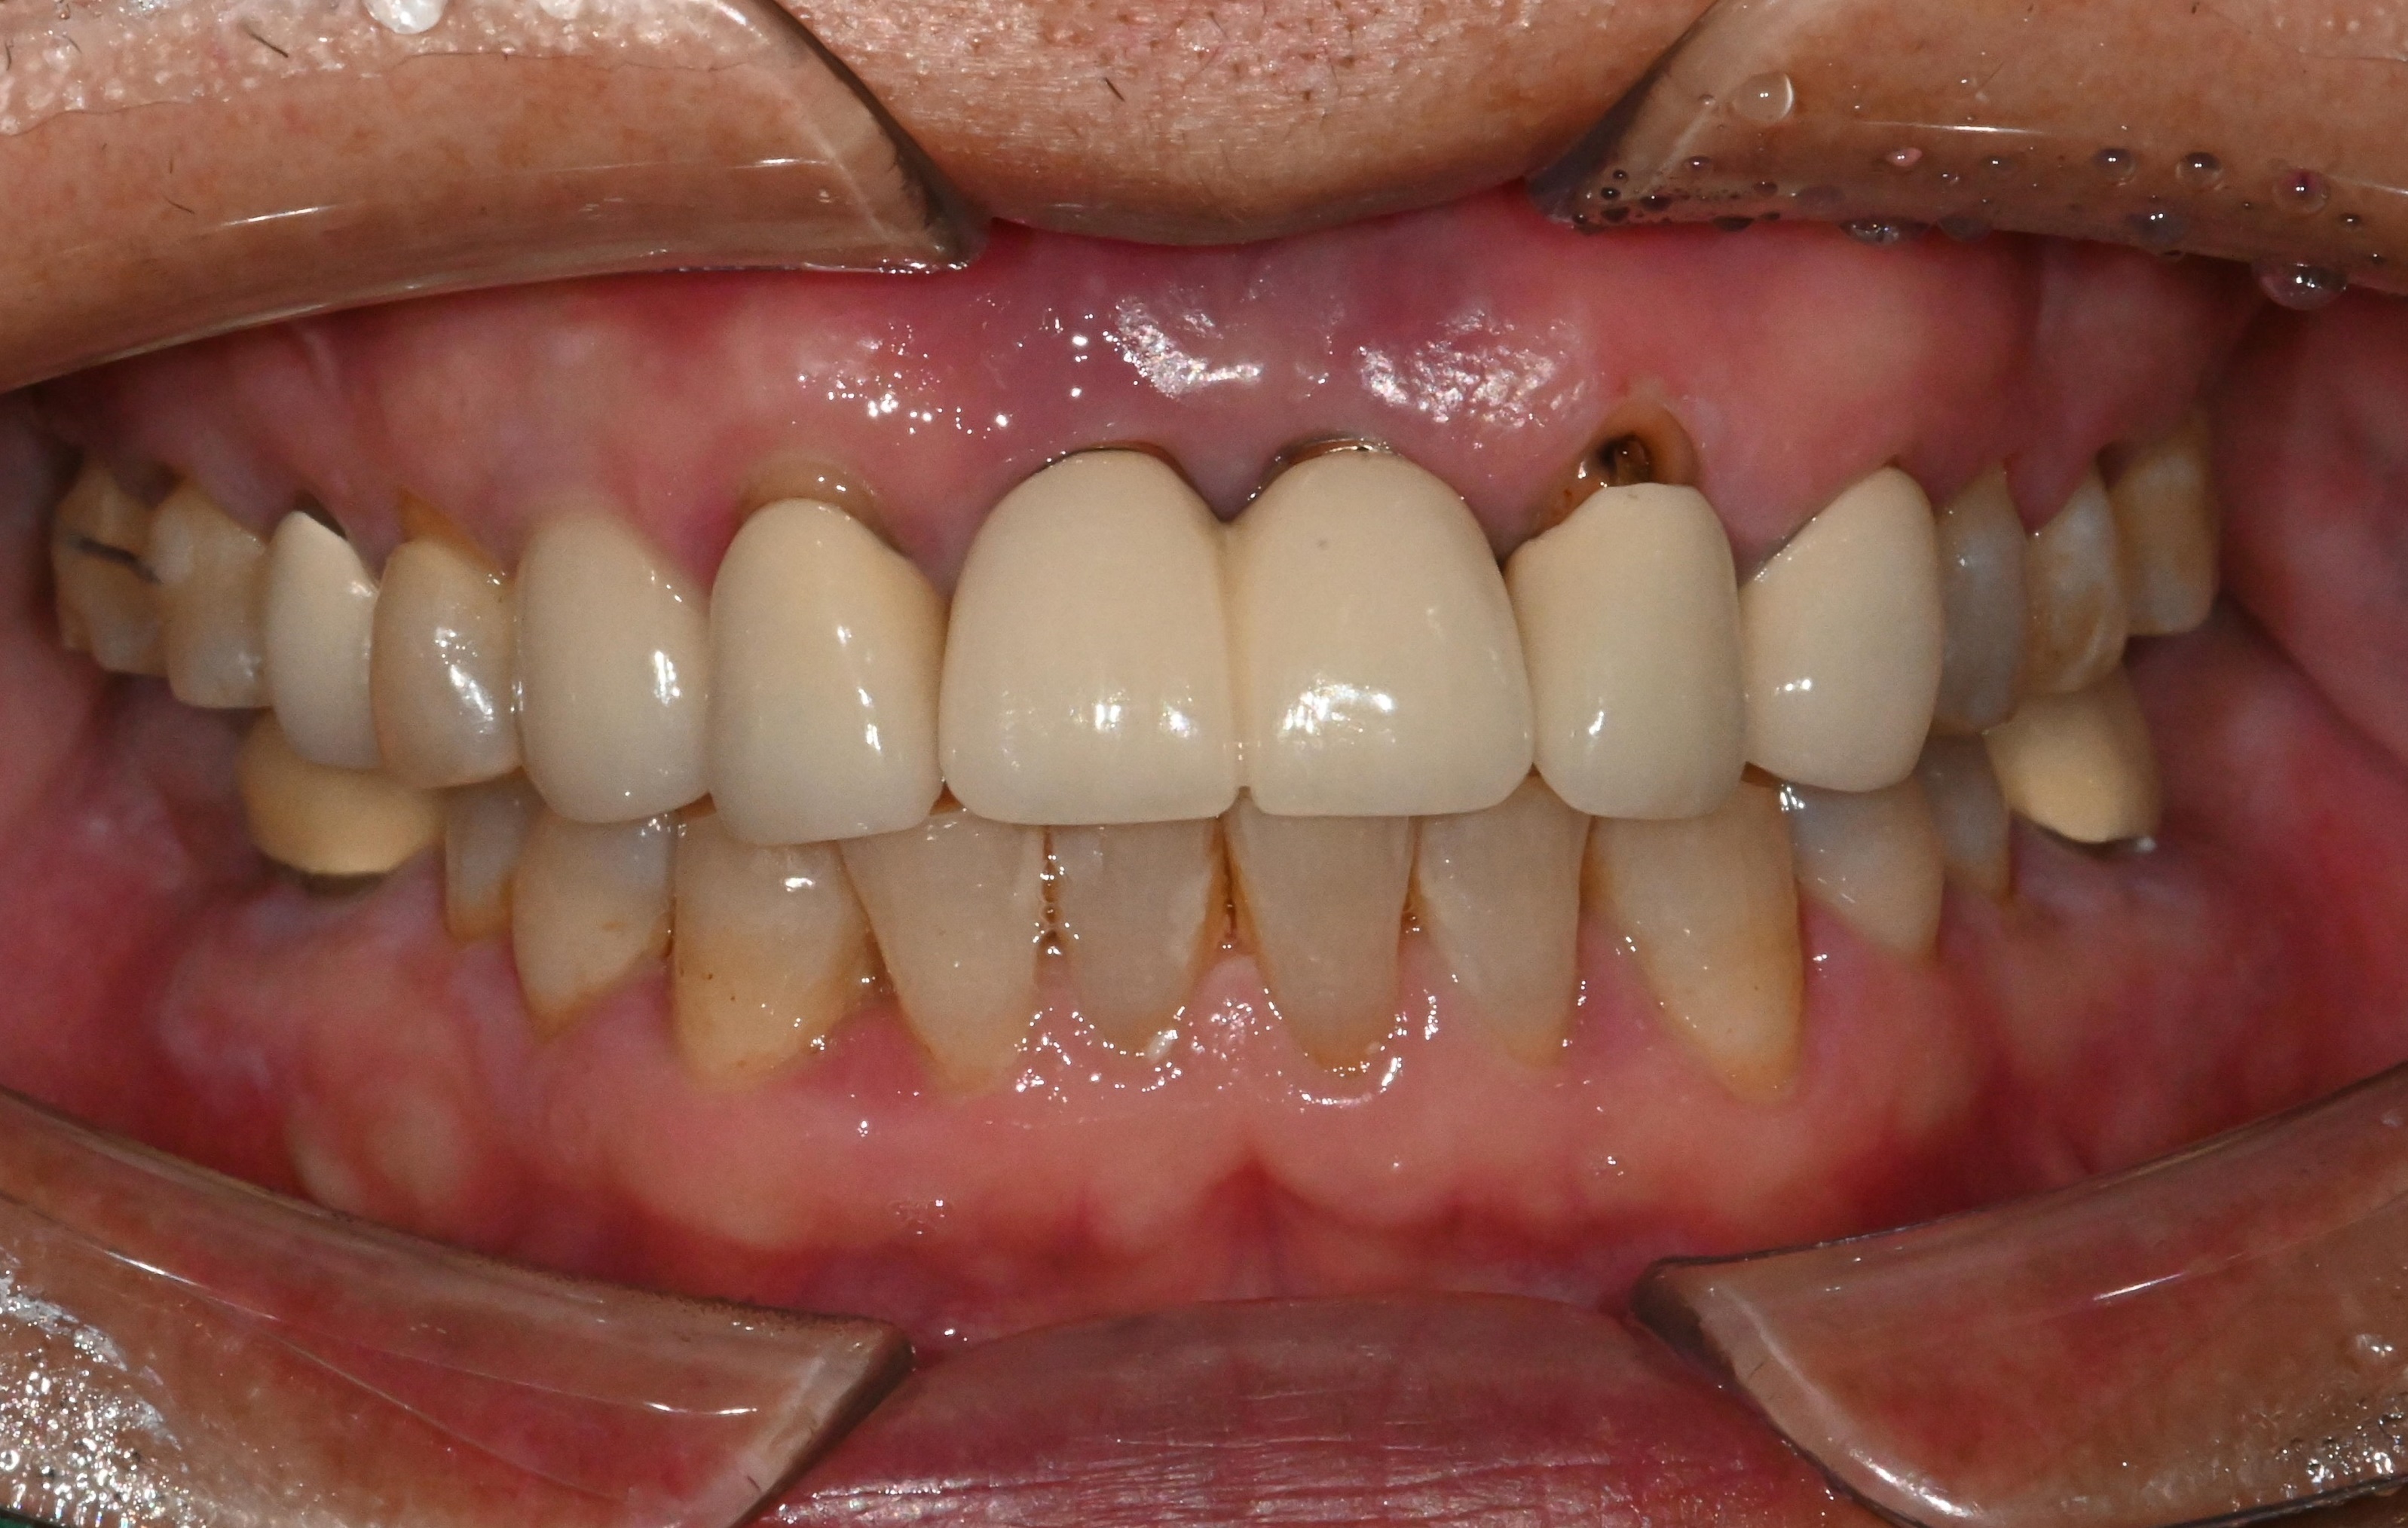

진단해보니,

잇몸 색이 푸르딩딩하게 변해있네요..

이는 인공치변 주변 염증

진행되고 있다는 신호입니다.

전치부는 뼈가 워낙 얇기 때문에,

일반 금속치근을 심으면

처음 몇 년은 괜찮아도 5~10년 사이에

결과가 급격히 나빠지는 경우가

매우 흔합니다.

일반적인 픽스쳐가

오래 못 버티는 이유는

명확합니다.

뼈가 얇아 시간이 지나면 잇몸이 내려가고

나사선이 잇몸 밖으로 노출되면서

염증이 반복되고,

결국 뼈가 녹아내리는 구조죠.

실제로 환자분이 염증이 생긴 이유도

정확히 이 과정 때문입니다.